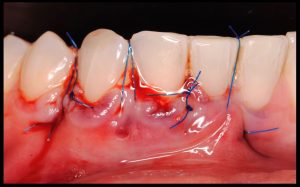

- Injerto de tejido conectivo libre desepitelizado de paladar + Tunelización

Fotografías del proceso: